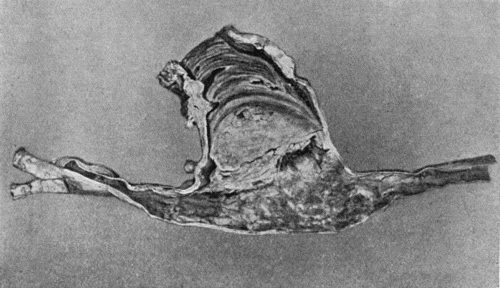

153.Epitheliomatus Ulcer of Leg invading Tibia 499

156.Caseating focus in Upper End of Fibula 513